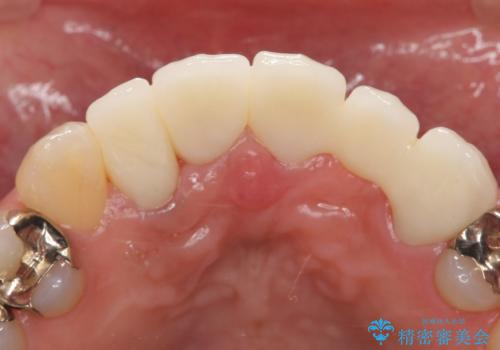

- 昔入れた被せ物と歯茎の間の隙間が気になると来院された方の症例です。

右上1、2番目の歯と左上1、2、3、番目の歯のブリッジを除去し、オールセラミッククラウンによる補綴を行うことで見た目を改善しました。

今回用いたオールセラミッククラウンはジルコニアフレームという白い素材の上にセラミックを盛っているため、審美性が非常に高いのが特徴です。

また、ジルコニアは人工ダイヤモンドの材料にも使われているほど高い強度を持っており、そのためオールセラミッククラウンは審美性だけでなく、奥歯やブリッジの補綴も可能とするクラウンです。